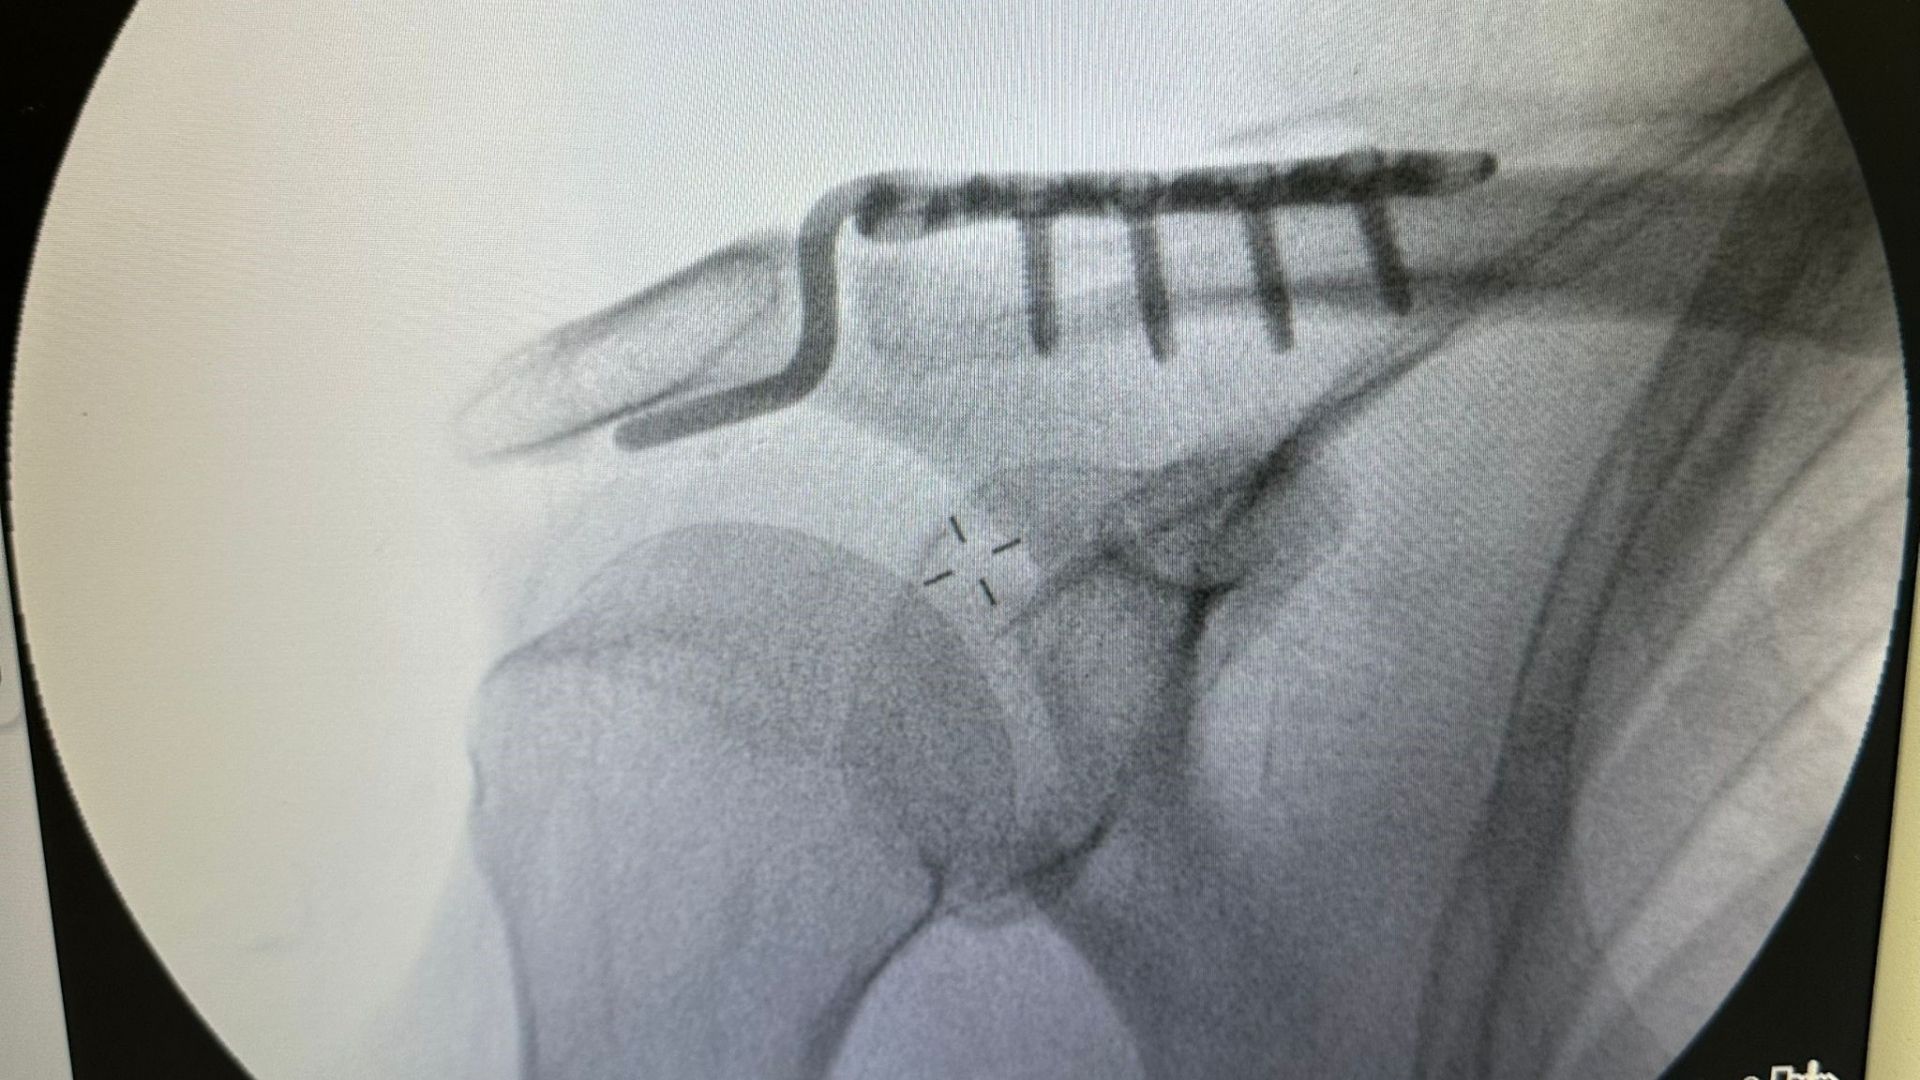

“Hastamız arkadaşlarıyla tenis oynarken omuz üzerine düşme sonrası çıkık gelişti. Normalde bu tabloyu genç hastalarda görürüz. Ancak kemik yapısına tam uyumlu, özel şekilli çengel bir plakla başarılı bir ameliyat gerçekleştirdik.”